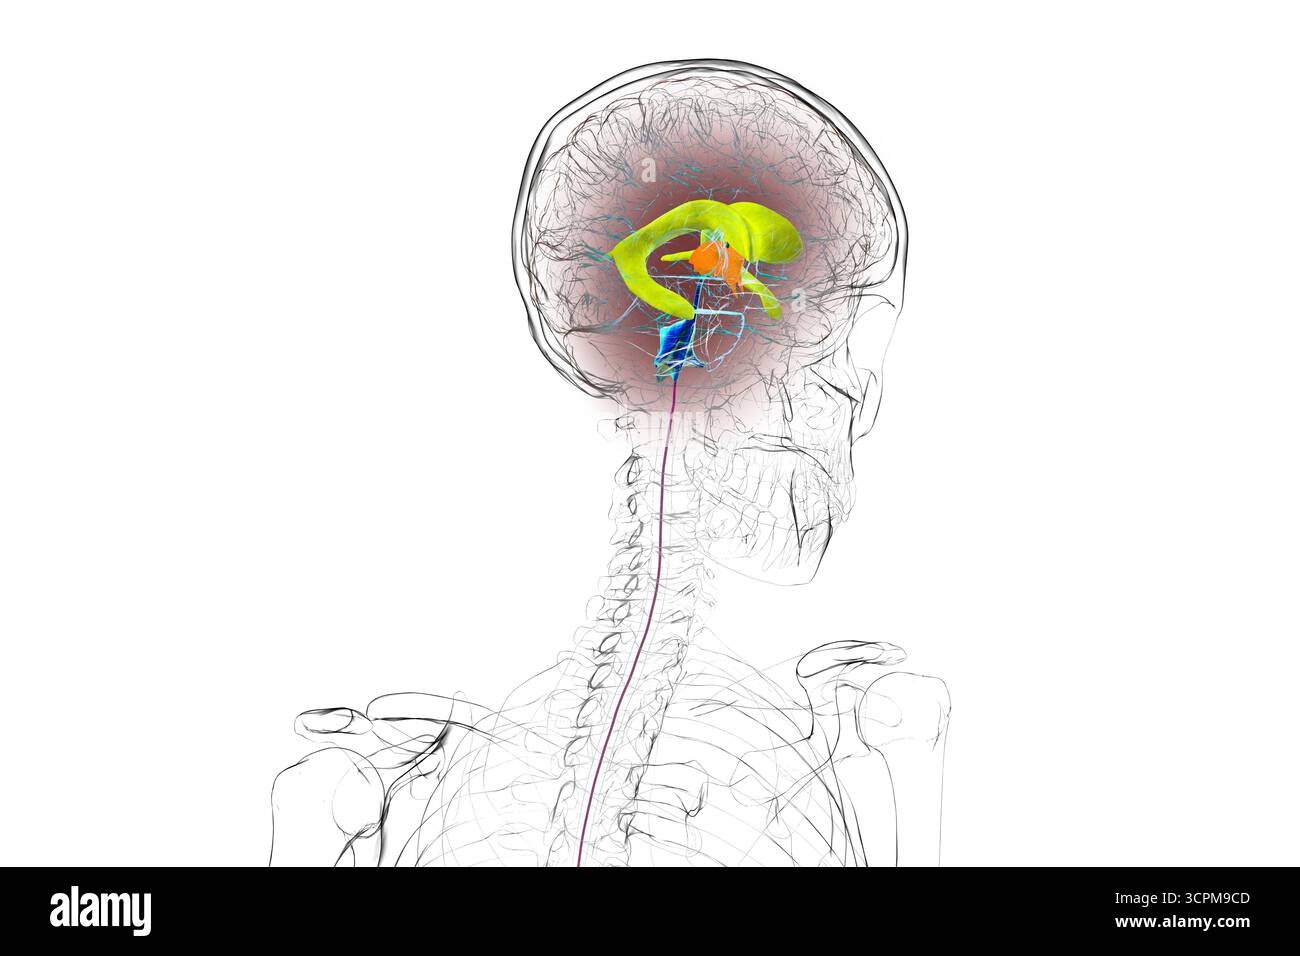

RF3CPM9D1–Abbildung des menschlichen Gehirns mit farbigen Ventrikeln: Lateral (gelb), dritter (orange), vierter (blau), interventrikuläres Foramen (grün), cerebral

RF3CPM9CD–Abbildung des menschlichen Gehirns mit farbigen Ventrikeln: Lateral (gelb), dritter (orange), vierter (blau), interventrikuläres Foramen (grün), cerebral